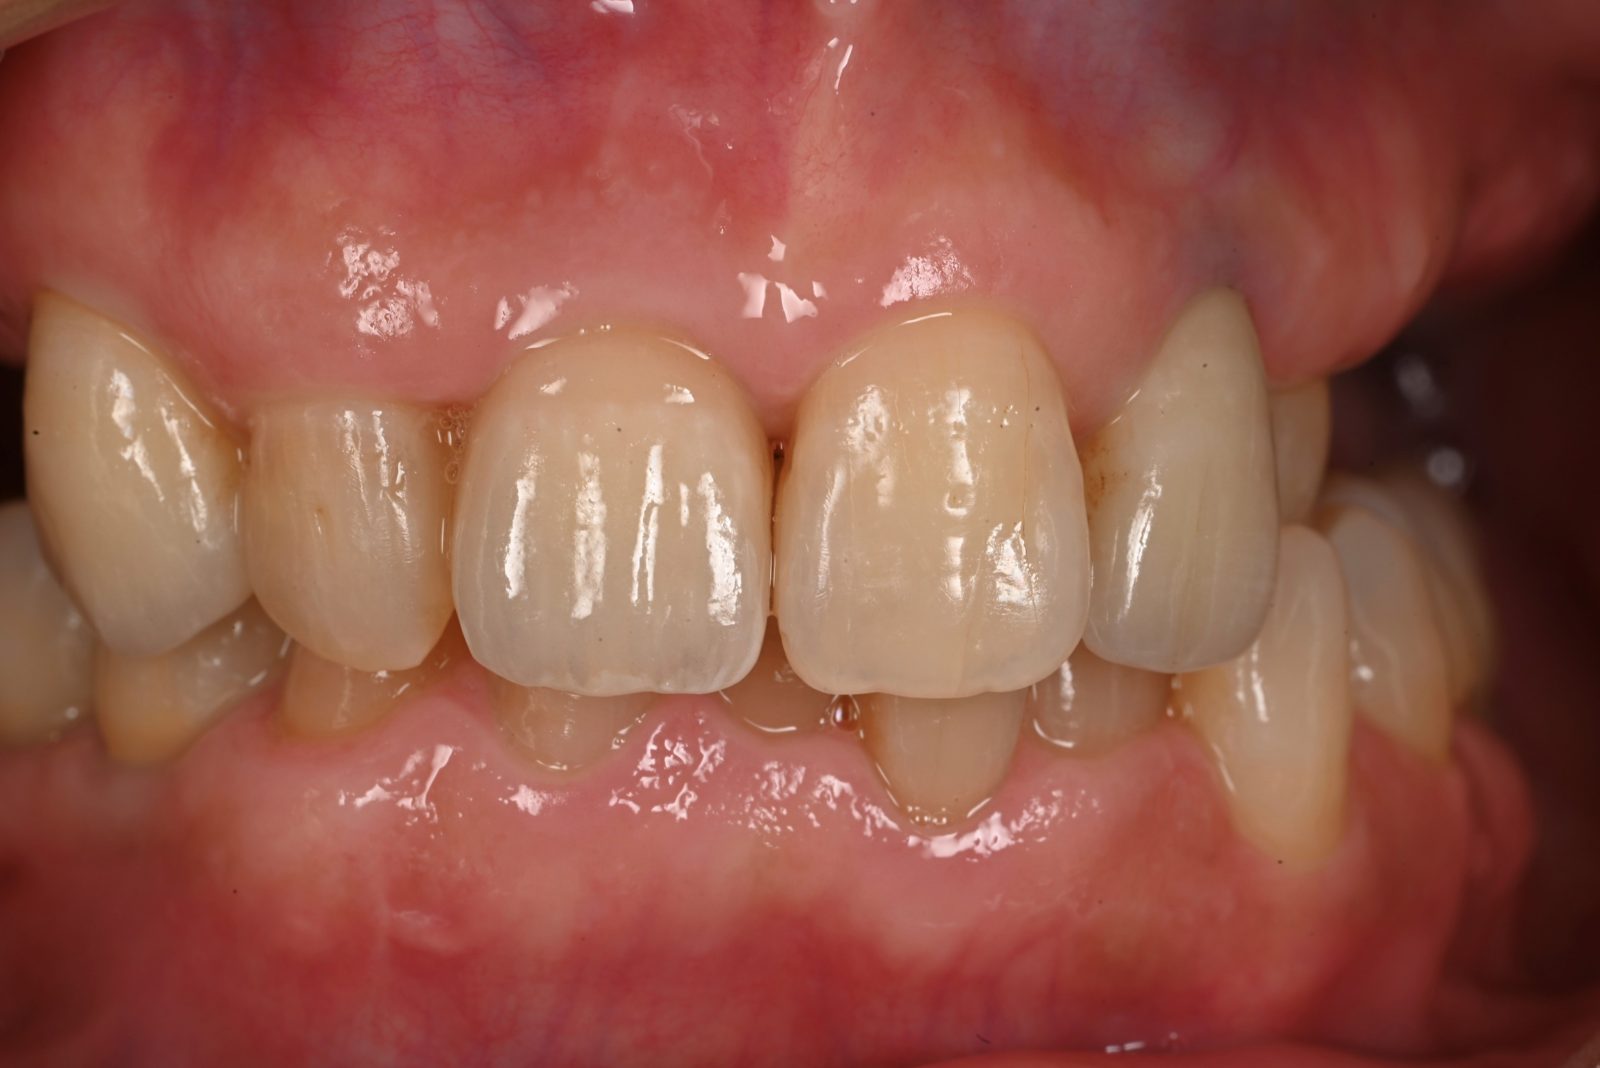

• 治療前

• 治療後